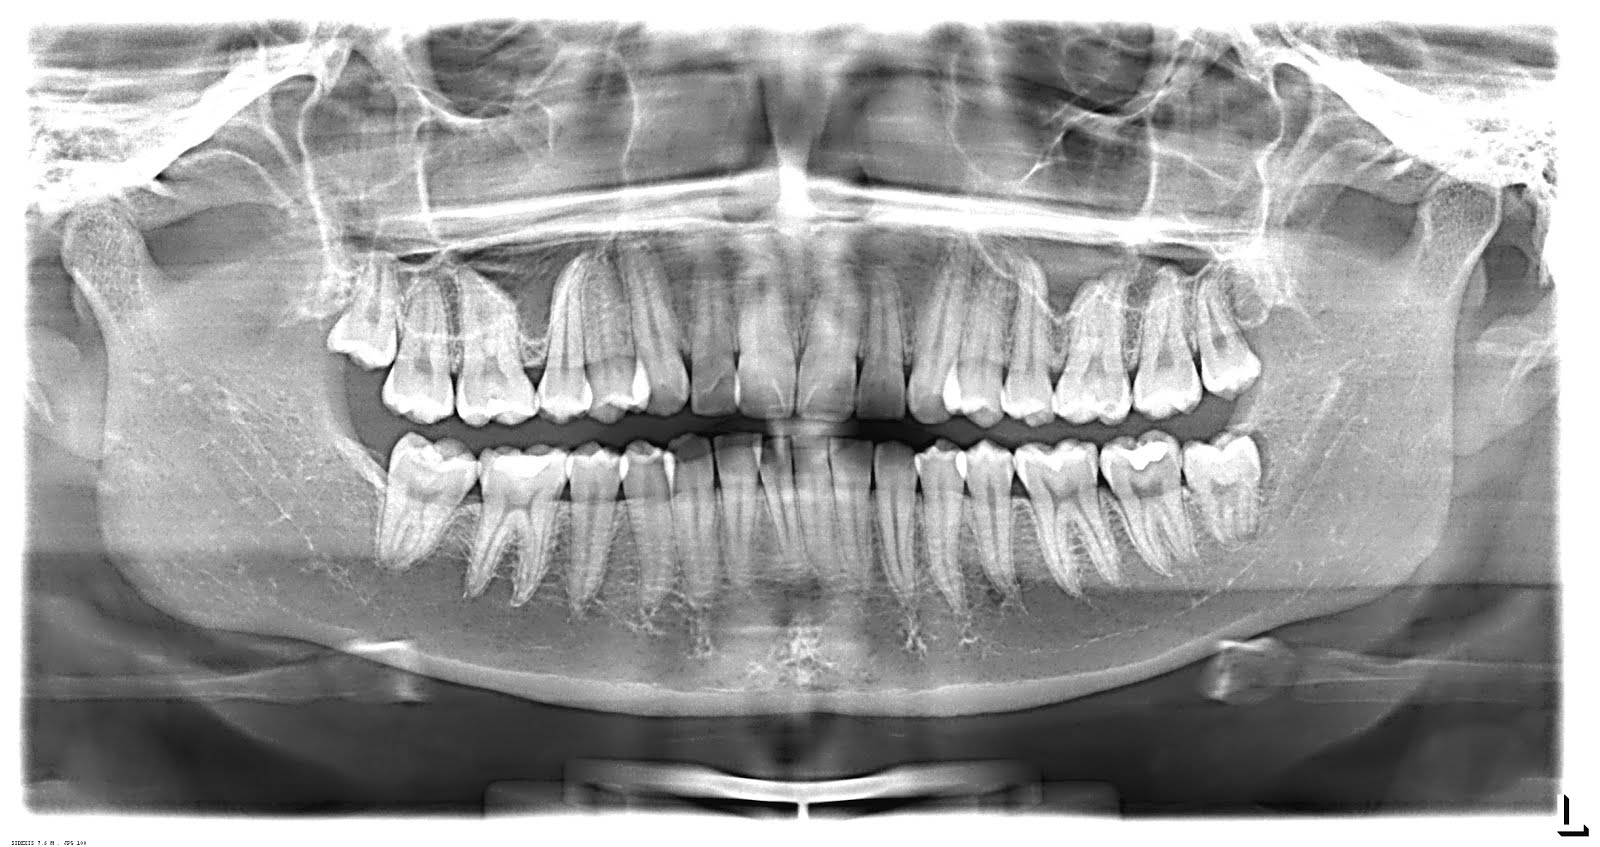

Las radiografías dentales son un tipo de imagen de los dientes y la boca.

California dental association 1201 k street, sacramento, ca 95814 800.cda.smile cda.org ® panorámica (panorex) una panorámica es una radiografía que se toma sin colocar la placa radiográfica dentro de la boca. La imagen radiogrfica es el resultado de la superimposicin del diente, hueso y tejidos blandos en el trayecto entre el cono del. Estas radiografías son enviadas a un ordenador, que genera una imagen virtual en 3 dimensiones de la boca del paciente. Imagen resultante del conjunto de índices absorcionales distintos que se forman a través de líneas simples o radioopacas y áreas

A cualquier edad esta radiografía permitirá saber la salud dental del paciente a nivel de dientes y huesos maxilares. Es importante en el diagnóstico en ortodoncia la realización de fotografías al paciente. Click the start the download.